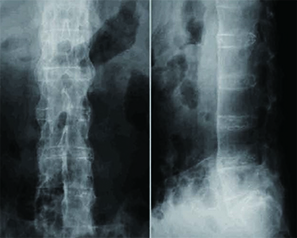

強直性脊椎炎を疑う場合、レントゲン写真やMRI検査を行います。

特徴的な痛みに加え、レントゲン写真で仙腸関節(骨盤の骨である仙骨と腸骨との間の関節)の変化が見られれば、強直性脊椎炎と診断することができます。

このほか、椎体の間の靭帯の骨化像が見られることがあります。